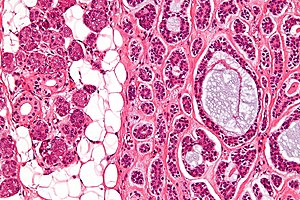

Adenoid cystic carcinoma. H&E stain. | |

| LM | cribriform architecture (other patterns: solid, cords, (bilayered) tubules), cystic spaces filled with basophilic material, scant cytoplasm in most cells, nucleus - small, hyaline stroma |

- Cribriform architecture or pseudoglandular spaces (classic pattern) - important feature.

- Other patterns: solid, cords, (bilayered) tubules.

- Cystic spaces filled with basophilic material (that is PAS +ve) - key feature.

- Scant cytoplasm in most cells (myoepithelial cells) - clear/eosinophilic.

- Moderate eosinophilic cytoplasm in the (rare) ductal cells.

- Nucleus - small.

- May be angulated (carrot-shaped) - myoepithelial cells; round/ovoid in ductal cells.

- Hyaline stroma.

The sections show a tumour with a cribriform architecture. The cystic spaces have basophilic material. The tumour cells are carrot-like and have scant/modest cytoplasm.